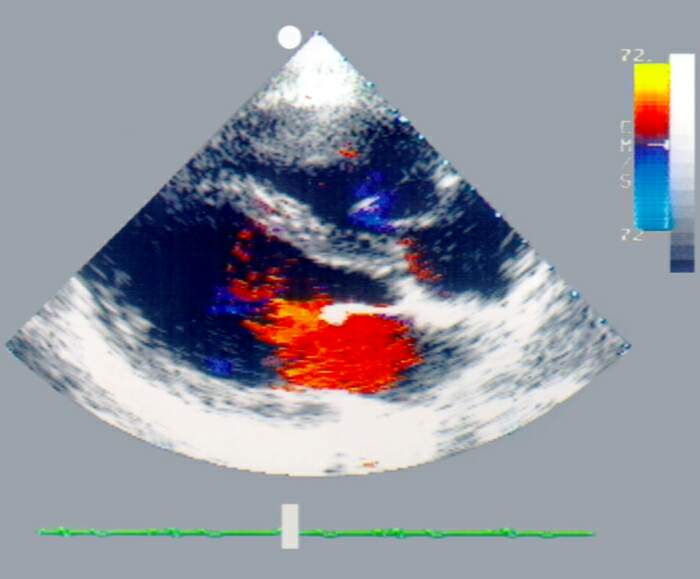

ДВУХМЕРНАЯ ЦВЕТНАЯ ДОППЛЕР-ЭХОКАРДИОГРАММА С ИЗОБРАЖЕНИЕМ СЕРДЦА В ПРОЕКЦИИ ДЛИННОЙ ОСИ

Рис. 6а). Двухмерная цветная допплер-эхокардиограмма с изображением сердца в проекции длинной оси: в период диастолы, красный цвет указывает направление потока крови в сторону датчика, поток соответствует фазе быстрого наполнения левого желудочка. Справа от эхокардиограммы видна цветовая шкала потоков и шкала акустической плотности.

Цветная двухмерная Допплер-эхокардиограмма отражает те же свойства потока крови, что и спектрограмма, но в процессе ее воспроизведения на экране осциллоскопа можно наблюдать движение потоков крови в сердце в реальном масштабе времени. При этом ламинарный поток крови, направленный к датчику, представлен на экране монитора одним цветом, например красным, от датчика — другим, например синим (рис. 6). Турбулентный поток имеет мозаичный вид с преобладанием зеленого цвета.